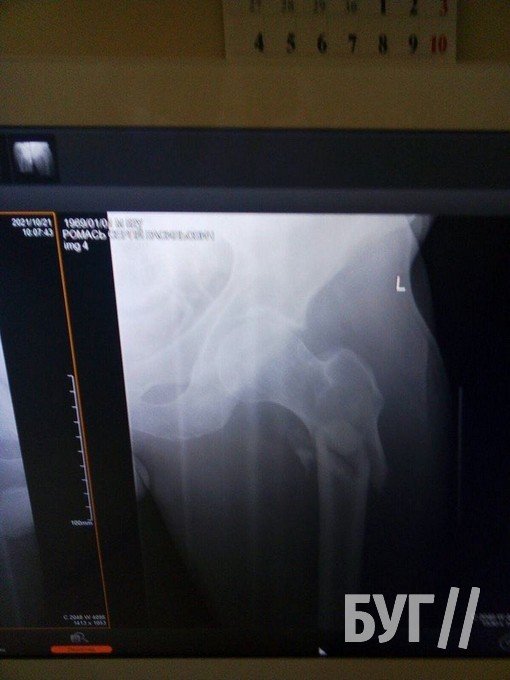

20 жовтня колишній шахтар Сергій Ромась отримав травму та потребує заміни суглоба і проведення операції на двох кінцівках.

У 52-річного чоловіка, який проживає у селі Суходоли, два переломи стегнових кісток і розтрощений кульшовий суглоб.